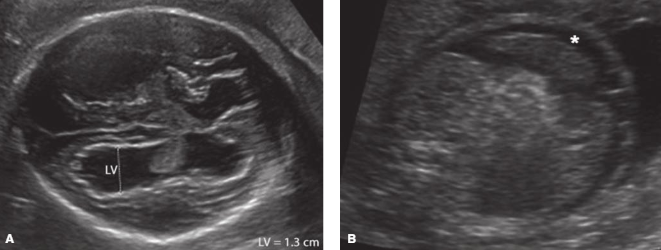

• 태아 임상 양상: 뇌실 주위 석회화, 뇌실 확장, 복수, 고에코 위장관, 흉수, 소두증, 태아 성장 제한, 간비장비대 등이 나타날 수 있다.

• A : 뇌실확장(LV = lateral ventricle), 뇌실 주위 석회화 / B : 복부 단면, 복수(*)와 고에코 위장관 소견